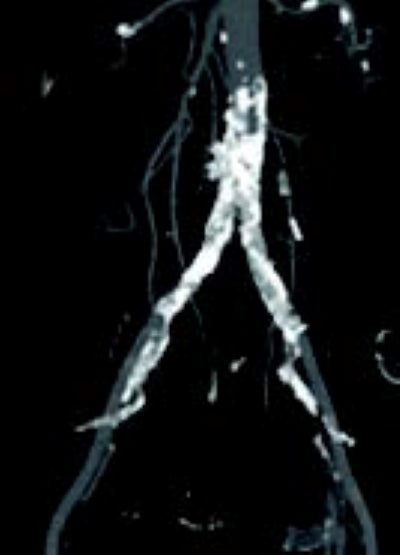

術前のCT(図1)と下肢造影(図2)より、大動脈遠位端の偏心性石灰化狭窄、右総腸骨動脈(CIA)の石灰化狭窄、左CIAの石灰化亜閉塞を認めた。大動脈からCIAの石灰化病変は連続しており、大動脈から両側CIAにかけてのキッシングステントが望ましいと判断した。腰痛が強く、術後安静が困難であるため両側橈骨動脈アプローチとした。

両側橈骨動脈より順行性に両側CIAにガイドワイヤーを通過させた。病変は偏心性石灰化でバルーン拡張により血管破裂のリスクがあることからVBXステントグラフト7.0 × 79 mm(6 Fr)を選択した。両側橈骨動脈からのアプローチにより(図4)スコアリングバルーンによる前拡張後(図5,6)、VBXステントグラフトを留置し(図4,7)、後拡張として高耐圧バルーン8.0 × 40 mmでキッシングバルーンテクニック(KBT)を行った(図8)。この際に迷走神経反射により心拍数が39回/分となったことから、これ以上の径での拡張は危険と判断し、手技を終了した。VBXステントグラフト留置後(図9)と術後造影(図3)では良好な血流が確認された。